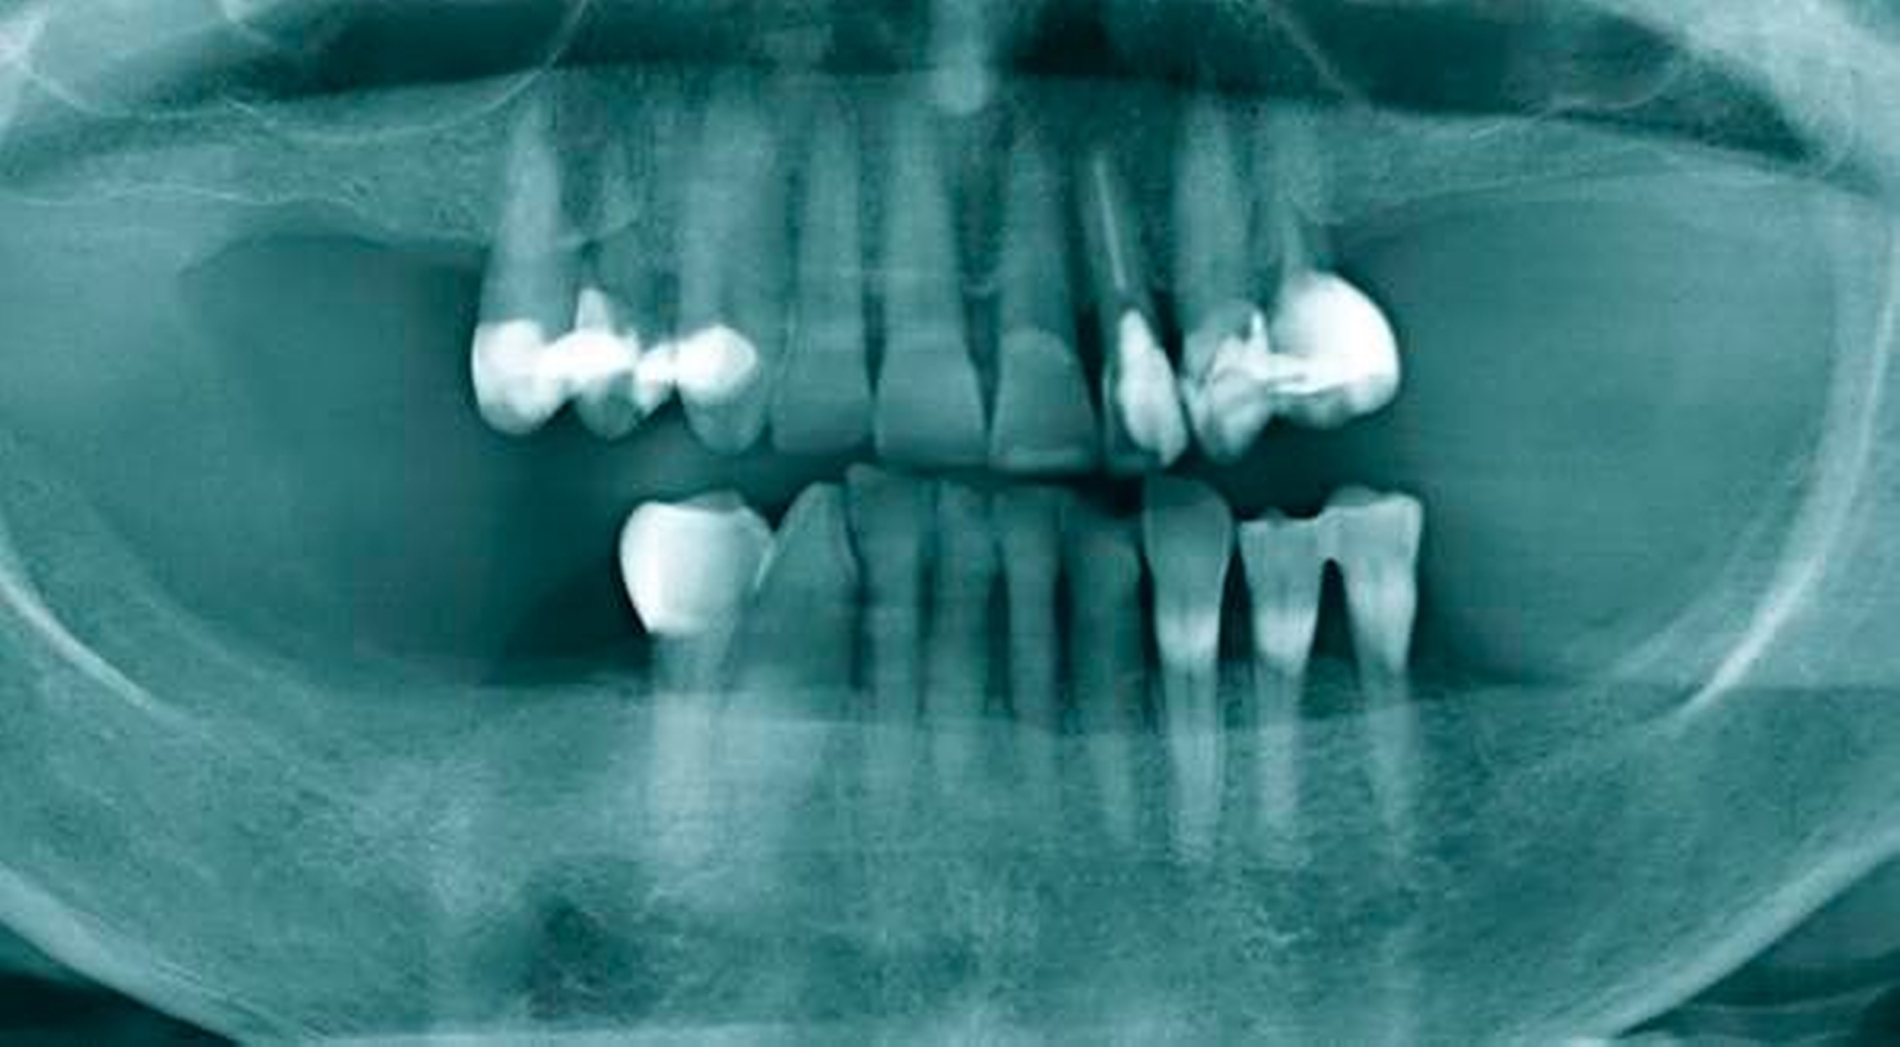

Abbildung 1a bis 1f: Direkte Überkronung im Frontzahnbereich (R1-Technik)

In den Abbildungen 1 bis 3 werden Optionen für frugale Interventionen auf restaurativem Sektor aufgeführt. Es handelt sich um direkte Vollüberkronungen im Frontzahnbereich (hier: hergestellt in R1-Technik / einphasig) (Abbildung 1), direkte Teilüberkronungen im Seitenzahnbereich (hier: hergestellt in R1-Technik / einphasig) (Abbildung 2), Reparatur-Restaurationen im Seitenzahnbereich (hier: hergestellt in R2-Technik / zweiphasig) (Abbildung 3). Technische Einzelheiten zur Vorgehensweise und den Ergebnissen sind an anderer Stelle beschrieben (Literatur siehe oben).

Am Beispiel von Abbildung 1 (stark zerstörte Zahnkrone eines Schneidezahns) kann das Prinzip der frugalen Intervention erläutert werden:

Früher wurde für die hier beschriebene Ausgangssituation folgendes Procedere gewählt:

Wurzelkanalbehandlung des vitalen Zahns als Voraussetzung für eine Stiftversorgung

Einsetzen eines Wurzelkanalstifts

Einsetzen einer indirekt gefertigten Stiftkrone

Durch die Erfolge der Adhäsiv- und Komposittechnik kann heute folgendermaßen vorgegangen werden:

Verzicht auf Wurzelkanalbehandlung / Erhaltung der Vitalität des Zahns

Verzicht auf Wurzelkanalstift

direkte minimalinvasive Kompositkrone (Verzicht auf indirekte Vorgehensweise)

Die potenziellen medizinischen und ökonomischen Vorteile dieser frugalen Intervention sind vielfältig:

Schonend: Die oralen Strukturen werden geschont und die Versorgung ist hinreichend stabil. Durch den Verzicht auf Wurzelkanalstifte wird das Wurzelfrakturrisiko reduziert. Zudem können Material-, Geräte- und Personalressourcen aus Praxis und Techniklabor, die beim klassischen Vorgehen anfielen, reduziert werden.

Bezahlbar: Hier ist anzumerken, dass die Kosten unter anderem von der zahnärztlichen Expertise abhängig sind: Zahnärzte, die mit direkten Restaurationen große Erfahrung haben, können zügiger und mit besserem Erfolg arbeiten als Kollegen mit geringerer Erfahrung auf diesem Gebiet; die Behandlung ist gleichwohl anspruchsvoll und deshalb nicht „billig“. Eine direkte Vorgehensweise kann, muss aber nicht automatisch zeit- und kostensparender sein als eine Versorgung mit indirekt hergestellten Werkstücken.

Gut genug: Ästhetische Feinheiten lassen sich bei direkten Restaurationen nicht immer in gleicher Perfektion einarbeiten wie bei indirekt gefertigten Kronen, auch die Stabilität des Hochglanzes lässt bei einigen Kompositpräparaten noch zu wünschen übrig. Andererseits erlauben die direkten Verfahren inzwischen mitunter sehr flexible Vorgehensweisen, die sich auch mit Farb- und Formkorrekturen von Zähnen kombinieren lassen. Die Erwartungen eines großen Teils der Patienten werden hinreichend erfüllt und die Nutzen-Risiko-Relationen wie auch die Aufwand-Kosten-Relationen erscheinen – wenn auch nicht durchgängig – so doch zumindest in vielen Fällen günstig.